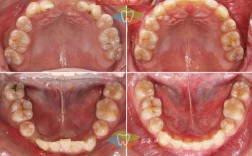

- 牙齿拥挤: 牙齿数量过多或颌骨空间不足,导致牙齿排列不齐、重叠。

- 口内/面部照片: 记录初始状态。